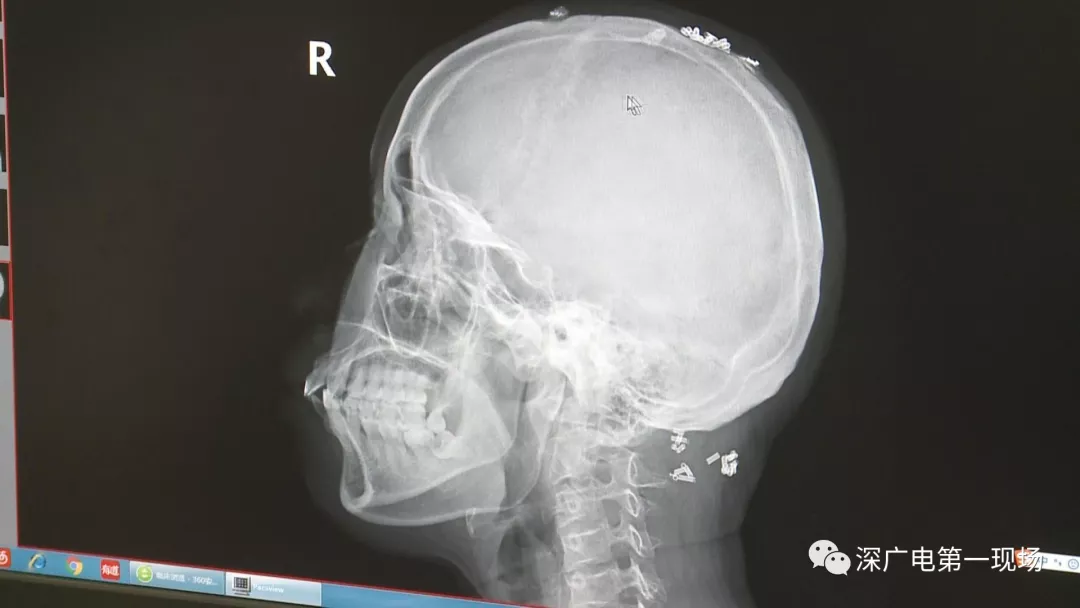

從X光影像圖片中可以看到

患者周身布滿了彈簧圈

深圳大學(xué)總醫(yī)院神經(jīng)外科副主任醫(yī)師陳富勇介紹,當(dāng)時檢查的時候發(fā)現(xiàn),該患者從頭部到腿部,基本上每個地方都有彈簧,很難數(shù)清具體數(shù)目。